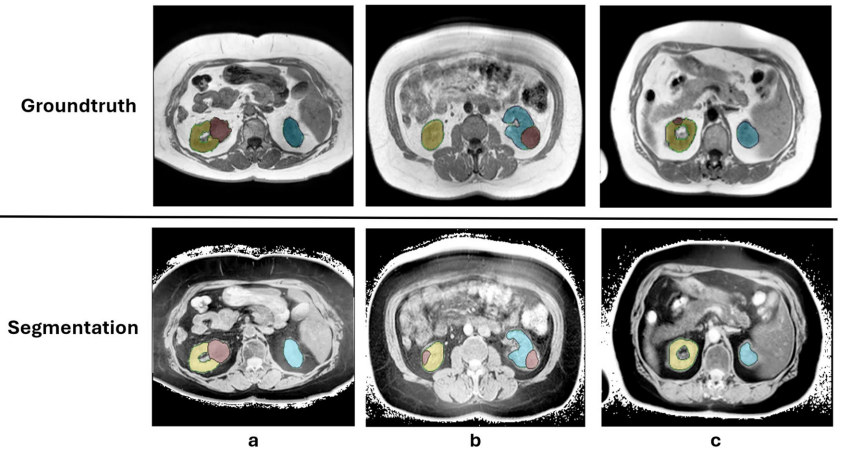

肾肿瘤模型的特异性表现

针对肾肿瘤模型,研究人员重点评估了三个特定类别:肿瘤、邻近正常肾脏(AN)和对侧正常肾脏(CN)。在未处理的T1w MRI中,模型无法正确分割任何这三个类别(DSC≤0.03)。在未处理的T2wfs序列中,模型能够大致分割肾脏(AN的DSC为0.57,CN的DSC为0.63),但肿瘤分割仍不成功(DSC:0.12)。添加反转步骤并将背景设置为零后,T1w分割准确性显著提高(AN的DSC:0.71;CN的DSC:0.76;肿瘤的DSC:0.42),但阻碍了T2wfs序列中的分割(所有类别的DSC≤0.10)。

在特定的反转对比T1w图像中,75例扫描中肿瘤被正确定位,19例定位错误,6例未检测到。这些组中肿瘤的中位体积分别为35 cm3、23 cm3和6 cm3。体积低于中位值29 cm3的肿瘤分割DSC为0.22,而高于中位值的肿瘤分割DSC为0.62。Spearman等级相关显示肿瘤体积与DSC之间存在显著相关性(p<0.001)。